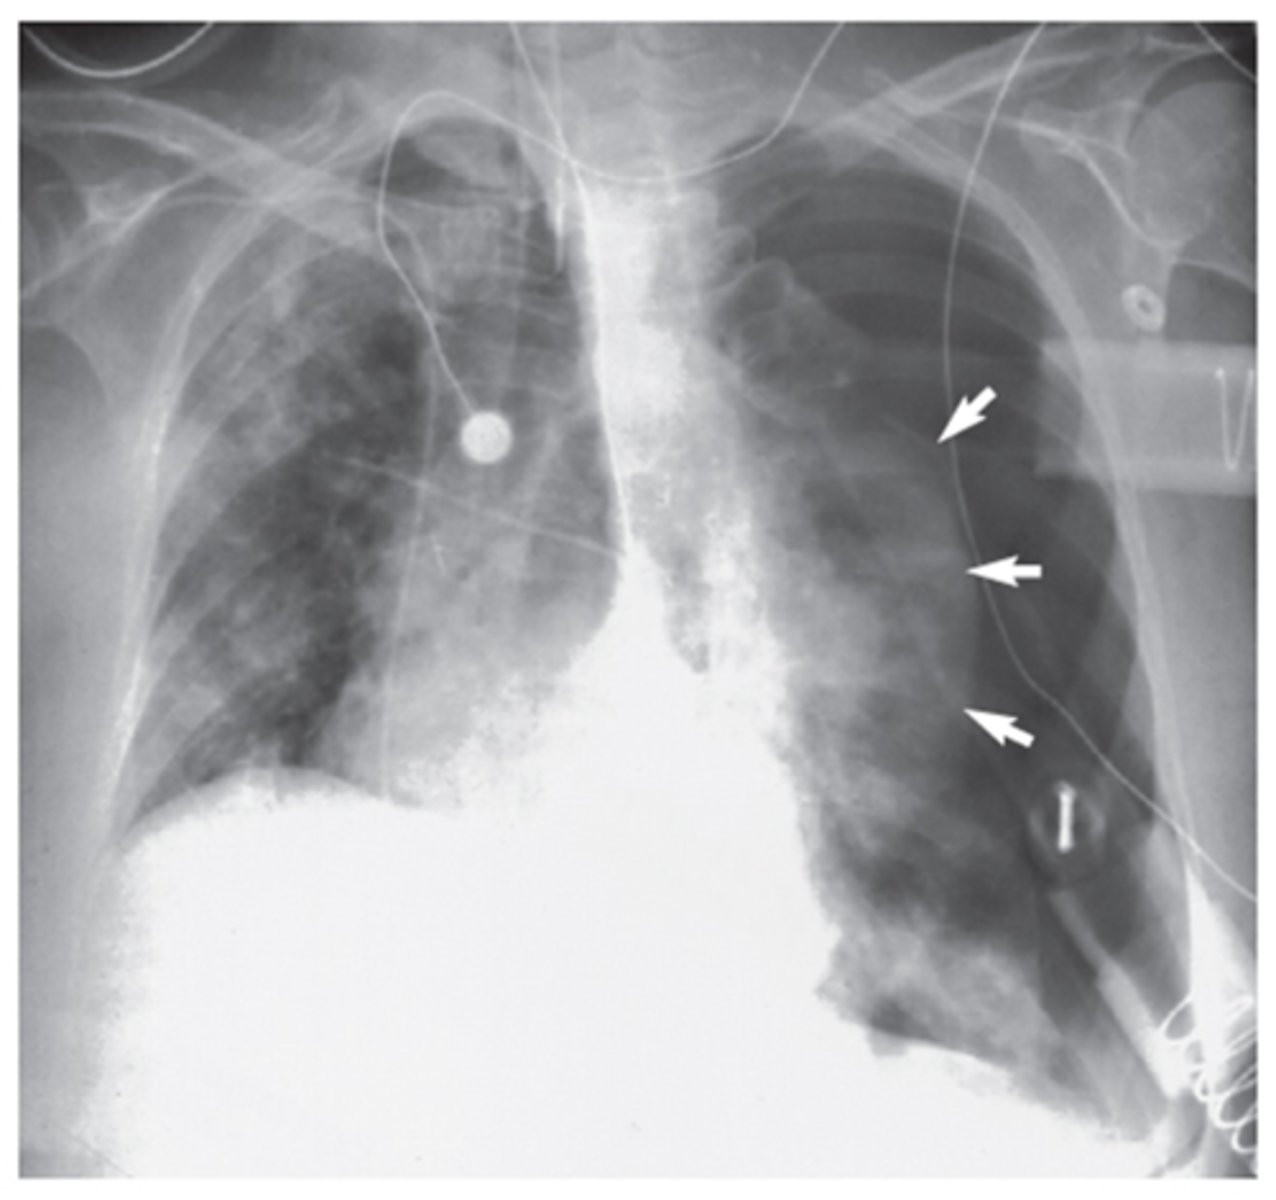

Pneumothorax (dark black area with no vessels)

Interpretation?

Tension pneumothorax (tracheal shift and lung shrunk)

Chest tube (tip of tube should be posterior and near apex of lung for drainage)

What is goin going on in this CXR?